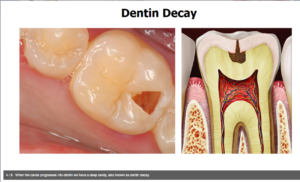

صورة ٣. تسوس طبقة العاج

الأحماض الآن تكون قادرة على الوصول إلى الطبقة الثانية من السن، والمسماة “العاج” (وهي الطبقة الوسطى من السن) وحين تصل عملية تسوس السن إلى هذه النقطة، تزداد وتيرة وسرعة تعفن السن، تدريجيا. وكلما استمر هذا الامر، تتقدم الجراثيم والأحماض في طريقها إلى داخل طبقات السن حتى تصل إلى لب السن أو عصب السن